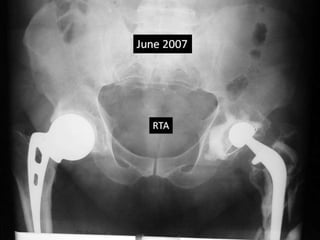

• Met with Road traffic accident in June 2007.

Case summary •36 yrs Male had Bilateral AVN hips • AMP done in 1988 rt side at the age of 36 yrs • Triad - cemented THR was done on left side in 1990 at the age of 38 yrs. • Advised revision of cup due to poly wear 2005 • Met with Road traffic accident in June 2007.

36 M AVN AMP – 1988 THR – 1990